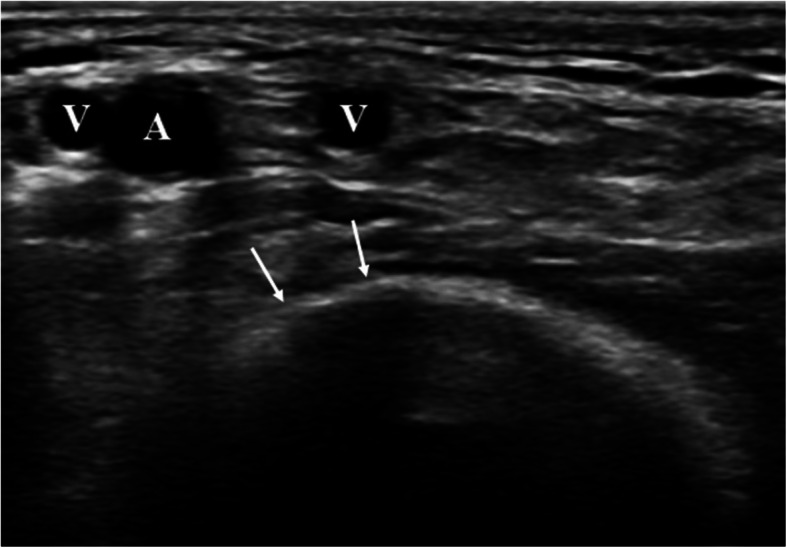

Fig. 1.

Transversal ultrasound picture of the A. brachialis (A) in the cubital fossa. The distal humerus (white arrows) forms an abutment, which helps for manual compressions. Two brachial veins (V) often accompany the distal A. brachialis

Our results indicate that the consistent use of ultrasound guide for brachial artery access results in a low number of access site complications (Fig. 3). Especially major complications that require surgical intervention appeared at a low rate of 2.7%. Moreover, brachial artery thrombosis resulting in upper extremity ischemia did not occur in our series. We hypothesize that with US-guidance, the brachial artery is punctured at the optimal location in proximity to the bony landmark of the medial humeral condyle away from arterial bifurcations. This leads to an optimal compressibility against the medial humeral condyle after removal of the sheath.